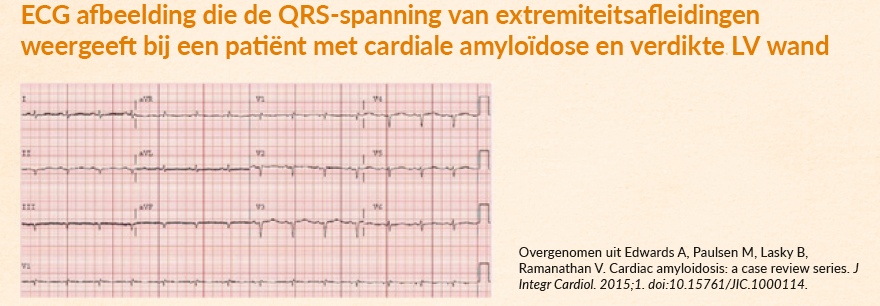

Het ECG

Beschrijving tonenEen bekend ECG-kenmerk van ATTRwt is een laag of normaal QRS-voltage, ondanks hypertrofie van het linkerventrikel.8

Hoe is dit te verklaren? Een verdikte wand is het gevolg van zich opstapelende amyloïdfibrillen, en niet van vergrootte hartspiercellen.8

Let op, bij cardiale amyloïdose is niet altijd sprake van de ‘klassieke’ lage QRS-voltages. Bij cardiale amyloïdose zien we een discrepantie tussen de toegenomen dikte van het myocard op een echo en de omvang van de voltages op het ECG. Het is daarom van belang om niet alleen naar lage voltages te zoeken. Waarom? Dit ECG-kenmerk is pas in een laat stadium van de ziekte waar te nemen. En dat maakt het wellicht minder nuttig om cardiale betrokkenheid snel te diagnosticeren.9

Figuur 1: Voorbeeld van ECG afbeelding die de QRS-spanning van extremiteitsafleidingen weergeeft bij een patiënt met cardiale amyloïdose en verdikte LV wand. -